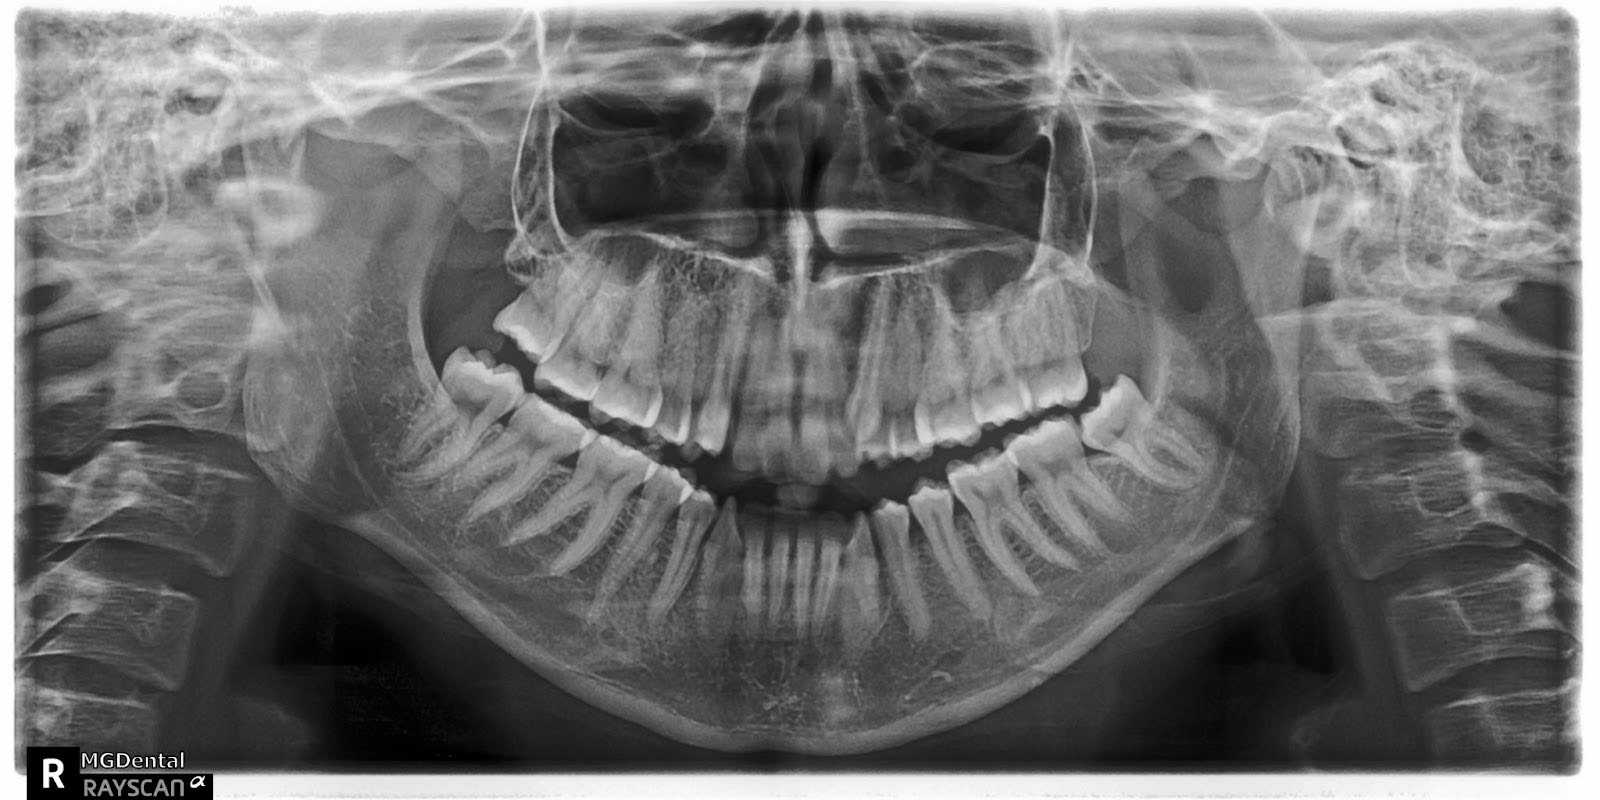

Une patiente de 27 ans présentant une malocclusion de classe III, un encombrement de 15 mm de l’arcade supérieure, une béance antérieure, une occlusion croisée latérale et un score ABO total de 29. Le profil facial était droit avec un maxillaire rétrusif. Les incisives supérieures et inférieures étaient rétroclinées. Un manque extrême de soutien du milieu du visage a été constaté. Des arcades dentaires rétrécies ont conduit à un sourire étroit et à des couloirs buccaux sombres. Aucune investigation myofonctionnelle n’a été réalisée, car le sujet n’était pas considéré à ce moment-là. Le Dr Coca a commencé à travailler sur la base de la philosophie de Damon en 2016. Pour le Dr Coca, ce cas présentait une courbe d’apprentissage, c’est pourquoi il pense qu’il est important de partager sa propre expérience, dans l’espoir que d’autres collègues lisant cet article bénéficient d’une meilleure expérience.

Étant donné le principe orthodontique du visage d’abord, l’objectif principal était d’augmenter le soutien du milieu du visage. Pour y parvenir, il a fallu développer le maxillaire supérieur, corriger l’occlusion croisée et aligner les dents. La fermeture de la béance était un objectif secondaire.

Le traitement ayant débuté en 2017 et le patient préférant une option de brackets moins visible, des brackets Damon Clear ont été utilisés. Des canines supérieures à couple élevé et des incisives supérieures à faible couple ont été choisies afin d’offrir le meilleur contrôle du couple pour le développement de l’arcade supérieure. Pour l’arcade inférieure, il n’y avait pas d’informations sur les autres possibilités de brackets. Des rampes de morsure ont été appliquées sur les deuxièmes molaires supérieures.

Les dents sont en très bonne position et l’os s’est remodelé.

Les changements faciaux sont impressionnants, étant donné que tout a été réalisé dans le cadre d’une orthodontie simple et qu’aucun appareil orthopédique ou orthopédique, TAD ou opération chirurgicale n’a été utilisé.

D’après l’expérience du Dr Coca, si une gestion appropriée de la force est obtenue, un remodelage osseux peut se produire et l’idée de limitation osseuse peut être au moins remise en question.